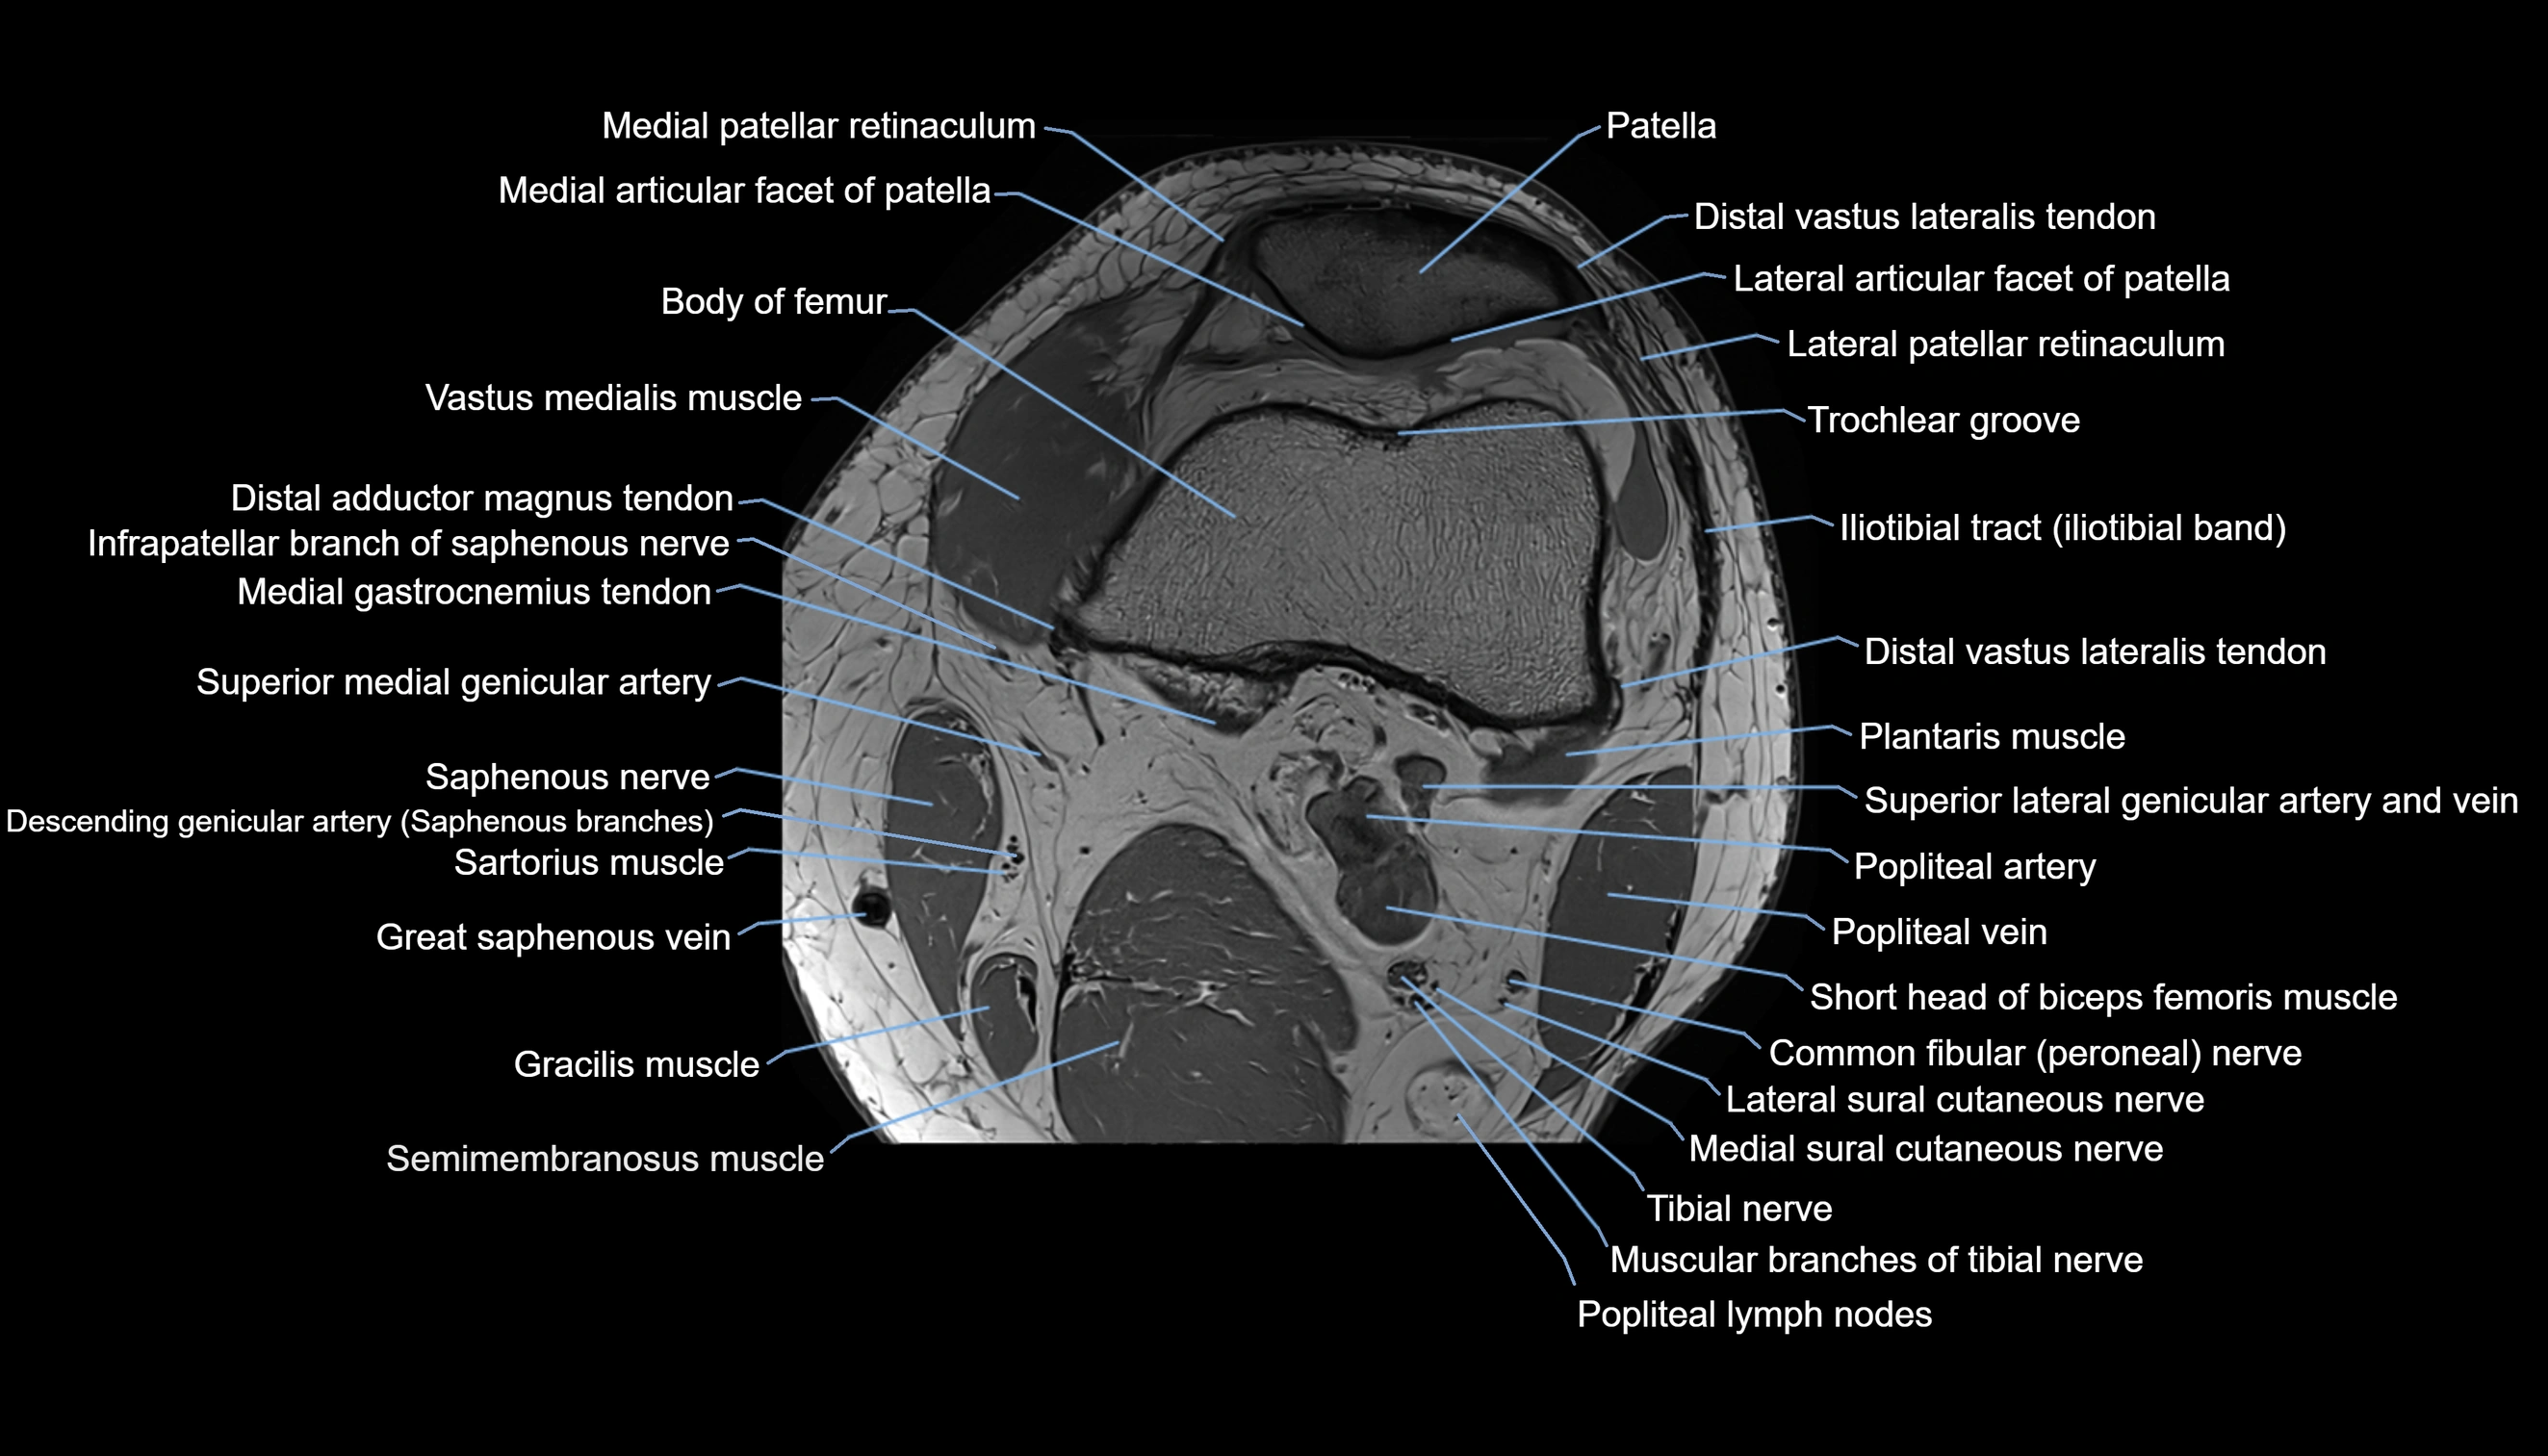

- Common fibular nerve

- Lateral articular facet of patella

- Lateral border of patella

- Lateral patellar retinaculum

- Lateral sural cutaneous nerve

- Medial articular facet of patella

- Medial patellar retinaculum

- Medial sural cutaneous nerve

- Muscular branches of tibial nerve

- Patella

- Popliteal artery

- Popliteal lymph nodes

- Popliteal vein

- Sartorius muscle

- Semimembranosus muscle

- Trochlear groove

- Vastus medialis muscle

- great saphenous vein